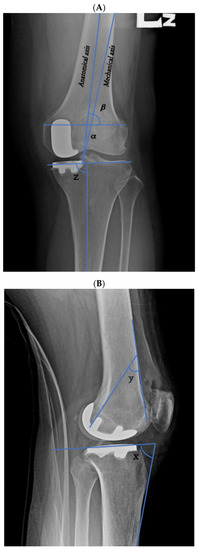

| Preanatomical axis angle (mean [SD]) | 3.26° ± 2.53° | 3.57° ± 2.49° | 0.519 |

| Postanatomical axis angle (mean [SD]) | 5.87° ± 3.5° | 2.81° ± 2.06° | <0.001 |

| Prefemoral condyle angle (mean [SD]) | 81.21° ± 2.41° | 81.12° ± 3.64° | 0.88 |

| Postfemoral condyle angle (mean [SD]) | 79.28° ± 4.19° | 79.15° ± 11.22° | 0.933 |

| Femoral implant angle (mean [SD]) | 30.04° ± 5.65° | 37.59° ± 5.4° | <0.001 |

| Pretibial axis angle (mean [SD]) | 86.39° ± 2.93° | 86.11° ± 2.56° | 0.598 |

| Posttibial axis angle (mean [SD]) | 87.57° ± 2.71° | 85.07° ± 1.76° | <0.001 |

| Pretibial slope angle (mean [SD]) | 12.48° ± 3.8° | 11.35° ± 3.19° | 0.093 |

| Posttibial slope (mean [SD]) | 10° ± 3.19° | 10.38° ± 3.32° | 0.535 |